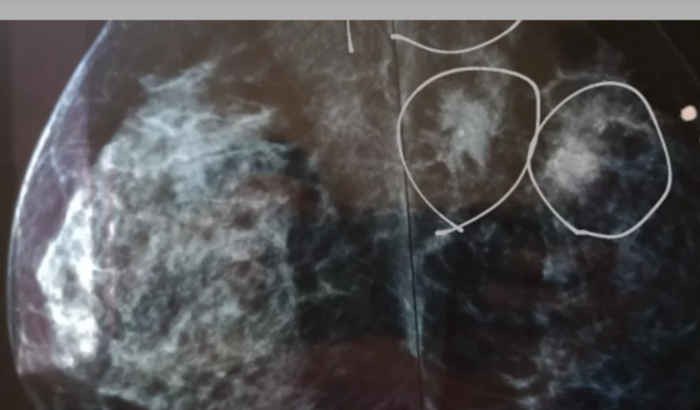

Preciso realizar um exame chamado pescândalo o sua tem mais nao tencontro muito tempo para saber se a doen a sé espalhou pelo meu corpo, sinto fortes dores de cabeca, estou com dificuldades para alamentou pos eStout dex-empregada as idas para o traramente das quimeo terapiasnão são baratos dependo de alguém, tenho 37 anos 2 filhos e tenho vontade de viver!